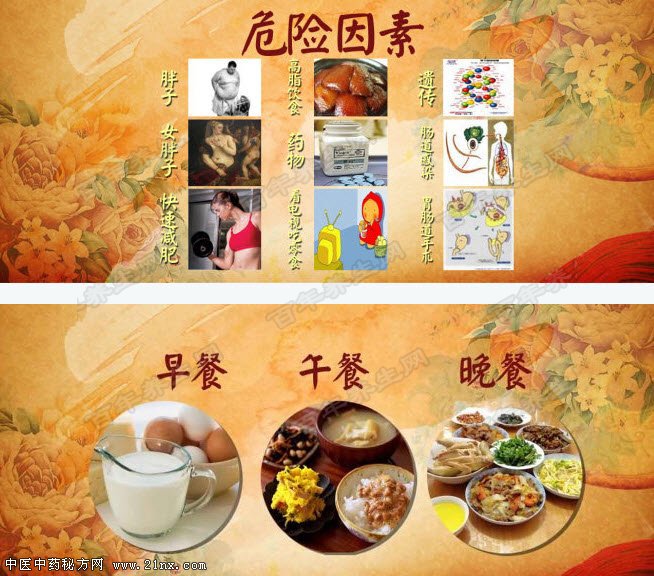

图:胆囊 胆囊疾病的发病率非常高,能达到10%以上,胖人比瘦人多发,且女性比男性多发,尤其是偏胖的女性更多发。 哪些情况是胆囊疾病的高危因素呢?胆囊疾病与高脂饮食密切相关,所以我们不仅要重视吃什么,还要特别注意怎么吃,针对健康人群和已患胆囊疾病的人群,您知道一日三餐中分别都是哪一餐需要特别注意吗?科学面对胆囊疾病,我们还能主动做些什么?

图:科学面对胆囊疾病 20160224养生堂视频和笔记:周丁华,胆囊息肉,胆结石,结肠癌,肝癌 |